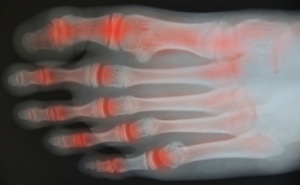

Toe Arthritis

If you are experiencing pain and discomfort in your big toe, you may have a foot condition that is known as toe arthritis. It may be caused by wearing shoes that are too tight and may not have adequate room for the toes to move about in. One of the first signs that may be indicative of toe arthritis may be pain that is felt in the toes. Many people feel stiffness in the toes, and this may be a result of the diminished cartilage that is located between the joints, in addition to obvious redness and swelling of the toes and surrounding area. If you are afflicted with this condition, it may be difficult to perform daily activities that may include walking or standing for extended periods of time. If you are experiencing arthritis in your feet or toes, it is suggested to speak with a podiatrist who can advise you on correct treatment options.

If you are experiencing pain and discomfort in your big toe, you may have a foot condition that is known as toe arthritis. It may be caused by wearing shoes that are too tight and may not have adequate room for the toes to move about in. One of the first signs that may be indicative of toe arthritis may be pain that is felt in the toes. Many people feel stiffness in the toes, and this may be a result of the diminished cartilage that is located between the joints, in addition to obvious redness and swelling of the toes and surrounding area. If you are afflicted with this condition, it may be difficult to perform daily activities that may include walking or standing for extended periods of time. If you are experiencing arthritis in your feet or toes, it is suggested to speak with a podiatrist who can advise you on correct treatment options.

Arthritis can be a difficult condition to live with. If you are seeking treatment, contact Dr. Michael T. Hames from Florence Foot Center. Our doctor can provide the care you need to keep you pain-free and on your feet.

Arthritic Foot Care

Arthritis is a term that is commonly used to describe joint pain. The condition itself can occur to anyone of any age, race, or gender, and there are over 100 types of it. Nevertheless, arthritis is more commonly found in women compared to men, and it is also more prevalent in those who are overweight. The causes of arthritis vary depending on which type of arthritis you have. Osteoarthritis for example, is often caused by injury, while rheumatoid arthritis is caused by a misdirected immune system.

Symptoms

- Swelling

- Pain

- Stiffness

- Decreased Range of Motion

Arthritic symptoms range in severity, and they may come and go. Some symptoms stay the same for several years but could potentially get worse with time. Severe cases of arthritis can prevent its sufferers from performing daily activities and make walking difficult.

Risk Factors

- Occupation – Occupations requiring repetitive knee movements have been linked to osteoarthritis

- Obesity – Excess weight can contribute to osteoarthritis development

- Infection – Microbial agents can infect the joints and trigger arthritis

- Joint Injuries – Damage to joints may lead to osteoarthritis

- Age – Risk increases with age

- Gender –Most types are more common in women

- Genetics – Arthritis can be hereditary

If you suspect your arthritis is affecting your feet, it is crucial that you see a podiatrist immediately. Your doctor will be able to address your specific case and help you decide which treatment method is best for you.